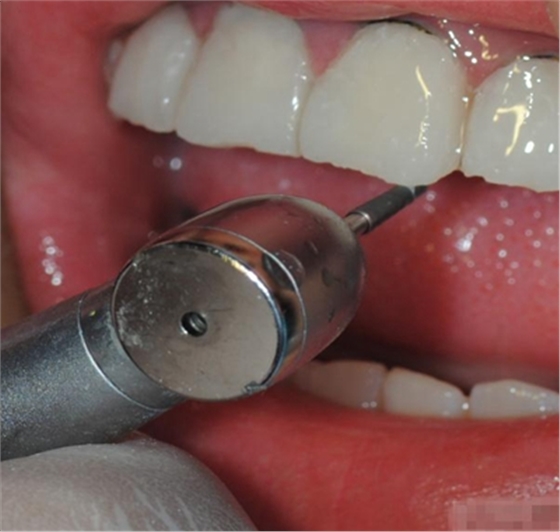

【初步修整】

對(duì)于唇面,首先使用火焰狀車針進(jìn)行修整,一般不使用輪狀車針修整線角

微細(xì)的表面結(jié)構(gòu)最后使用鎢鋼拋光車針成形的。

拋光目的:表面光滑 咬合關(guān)系 邊緣適應(yīng) 最少的菌斑附著 易于菌斑去除 美觀性

【纖維刷拋光】

脂拋光中應(yīng)注意:樹(shù)脂拋光放到24H后為最佳,因?yàn)榇藭r(shí)收縮應(yīng)力最為平衡,特別是在固化后10min內(nèi)應(yīng)避免對(duì)樹(shù)脂修復(fù)體進(jìn)行外力加載,包括打磨拋光及冷熱張力等,因?yàn)榇似陂g收縮應(yīng)力變化明顯,拋光時(shí)的機(jī)械應(yīng)力會(huì)使釉質(zhì)層形成裂隙。

最先選擇最粗的拋光碟去除多余的充填物 建立最初的解剖形態(tài). 10,000 rpm

使用中粗的拋光碟進(jìn)一步修整外形,建立邊緣脊和切邊. 10,000 rpm

選擇細(xì)的拋光碟進(jìn)行更進(jìn)一步的表面處理,并為最后的拋光準(zhǔn)備

用超細(xì)拋光碟進(jìn)行最終的拋光,最后完成的表面非常光潔,并且能夠保持很久。

【充填完成】

1、樹(shù)脂貼面平齊牙齦邊緣是最佳設(shè)計(jì),或者使用齦上邊緣 。

2、釉質(zhì)邊緣要用橡皮輪拋光。拋光可以去除懸釉。這樣經(jīng)過(guò)車針打磨過(guò)的釉質(zhì)表面會(huì)更加均一,形成良好的邊緣封閉。

3、纖維樁通常深入到根管的1/2至2/3處。因?yàn)樽罴训恼辰有Чl(fā)生于根管的冠1/3和中1/3。由于根1/3的牙本質(zhì)小管往往不能充分敞開(kāi),此區(qū)域幾乎沒(méi)有粘接作用發(fā)生,所以,根管纖維樁放置的深度無(wú)需超過(guò)根中1/3。

4、修整纖維樁按所需長(zhǎng)度裁截纖維樁 在有水條件下 用切割砂片或車針截取纖維樁,切勿使用鉗子,剪刀或鑷子以免破壞樁的結(jié)構(gòu)。

5、為了提高樹(shù)脂的聚合轉(zhuǎn)化率,我們可以用防氧化劑,或者用甘油涂沫于樹(shù)脂的表面,或者修復(fù)體的間隙處,以利于樹(shù)脂的聚合。然后再進(jìn)行打磨拋光。